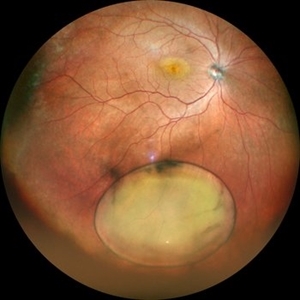

Dislocated IOL in Vitreous with RD

May 11 2020 by Gayathri Mohan

Color fundus photo montage of a patient showing a dislocated posterior chamber intraocular lens in the vitreous cavity inferiorly along with a sub total retinal detachment.

Photographer: Gayathri Mohan, Retina Foundation

Imaging device: Mirante, Nidek

Condition/keywords: dislocated posterior chamber intraocular lens (PCIOL), montage